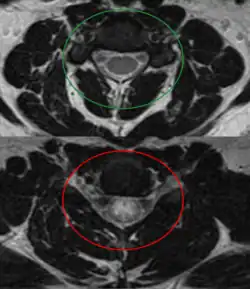

| An MRI showing a transverse myelitis lesion, which is lighter, oval shape at center-right. The patient recovered 3 months later. | |